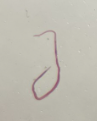

trematode miracidium

trematode redia

Trematode sporocyst

Schistosoma spp. cercaria